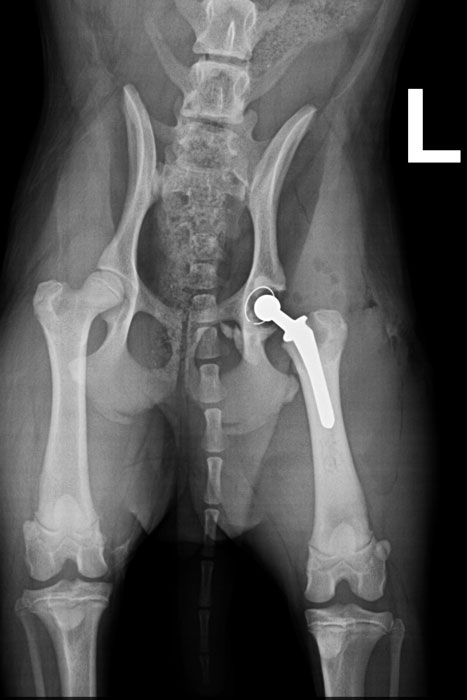

Röntgenbild nach der OP: neues Hüftgelenk mit 10 Millimeter großem Oberschenkelkopf.